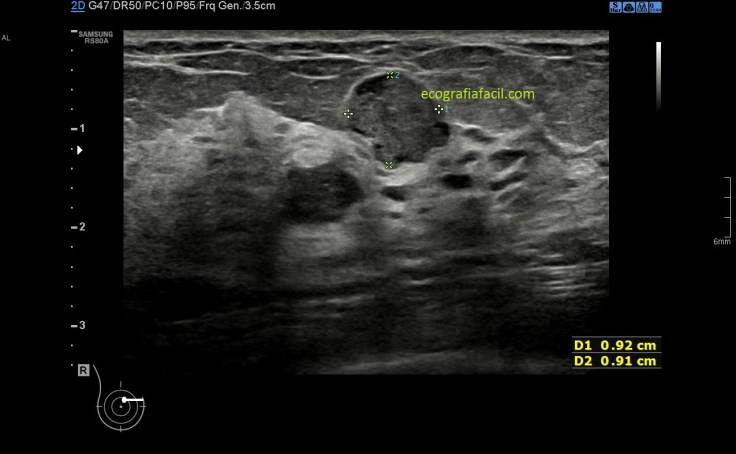

En la imagen 5 ves un conducto anecoico y como en su interior aparece una estructura hiperecogénica y nodular que no se mueve y que se puede estudiar en ambos planos, transverso y longitudinal y que ante tal hallazgo es medido y se le comprueba la presencia de vascularización, consideración que puedes ver en la 6,7 y 8. La flecha blanca indica normalidad.

Finalmente, en la imagen 6,7 y 8 puedes ver como un lesión nodular de grandes dimensiones ha crecido dentro de un conducto, al extremo de apreciarse la imagen nodular y no el conducto dilatado. Puedes ver que un gran contenido ecogénico ha crecido, que aún hay respetado en el ducto parte líquida, representada mínimamente por la parte anecoica del conjunto estudiado.

Ante los hallazgos de la imagen 5 y 6 la radióloga puede ampliar el estudio con punción guiada con ecografía que eventualmente y a su criterio puede ser PAAF, BAG o BAV. Punción con aguja fina, gruesa o con aguja de vacio, respectivamente. Es una decisión exclusiva de la radióloga.